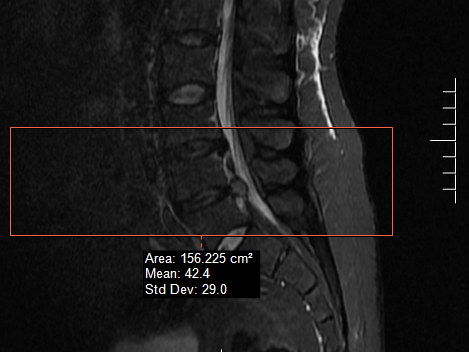

最近接诊了一位患者:小伙子今年30岁,162cm,86kg,3天前腰痛去外院检查怀疑肾结石打了几天针,症状未愈反加重,辗转来到国药东风总医院就诊。作为骨科医师,我很关注患者身形体态,估算BMI32.8,属肥胖体型。仔细查体,卧位下左下肢仅仅能抬离床面10度(正常人能达到70-90度),腰骶部疼痛,下肢麻木,跛行,初步诊断腰椎间盘突出。入院后患者下肢疼痛麻木症状持续加重,不能行走,迅速安排手术治疗,术中摘除了问题椎间盘植入融合器,患者术后下肢疼痛麻木症状很快消除,术后第一天即可站立,第二天行走无障碍。